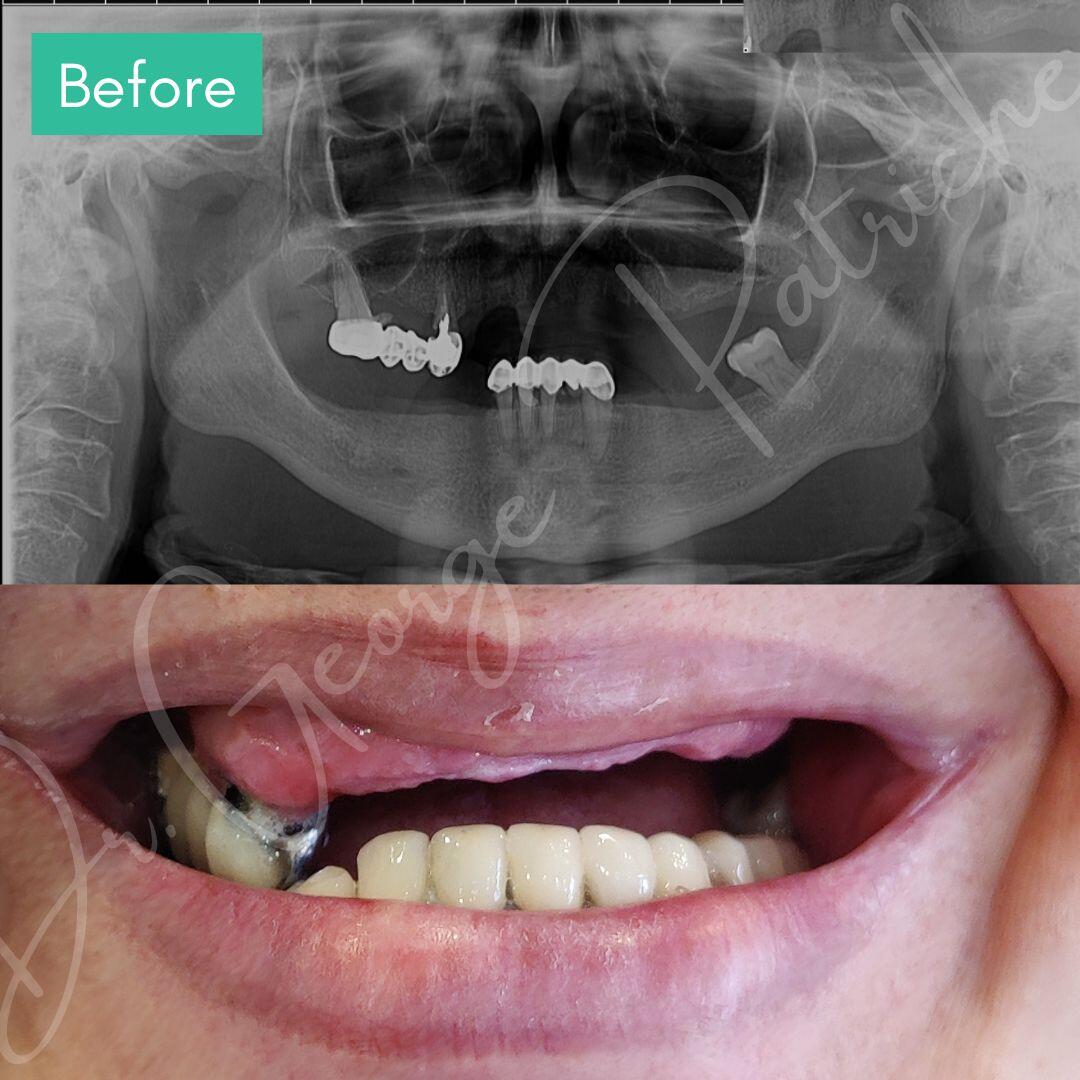

Before & After